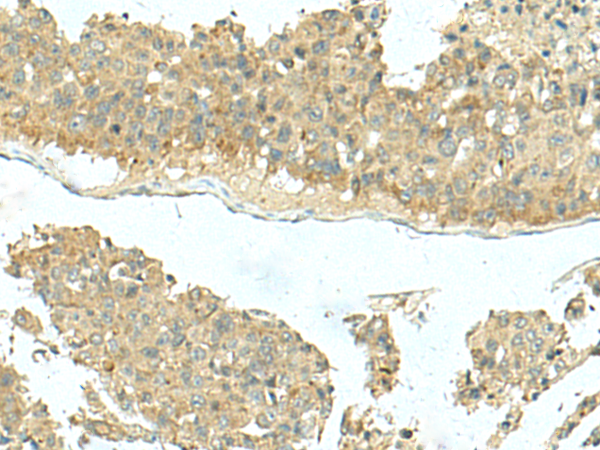

ELISA, WB, IHC

IHC positive control:

IHC Recommend dilution: